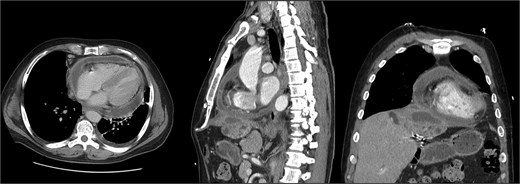

The patient presented the following day with fevers and new chest pain. He underwent a computed tomography angiography (CTA) chest and abdomen/pelvis, which revealed a left lower lobe consolidation and a moderate pericardial effusion. His hepatic abscess had increased in size to 7.2 × 5.5 cm (Fig. 2). Cardiology was consulted, and a bedside echo was performed, which found acute pericarditis. He was admitted and started on IV antibiotics and colchicine for his pericarditis. GI subsequently performed an ERCP, which showed no biliary or anastomotic stricture (Fig. 3). It was thought that it was likely a choledochal cyst, and the plan was for elective left hepatectomy. He was transitioned to oral antibiotics and discharged with colchicine for 3 months.

First readmission CT scans. (A) CTA chest images in the axial and sagittal planes illustrating the newly developed pericardial effusion. (B) CTA abdomen/pelvis images in the axial, coronal, and sagittal planes. These illustrate the abscess increasing in size.